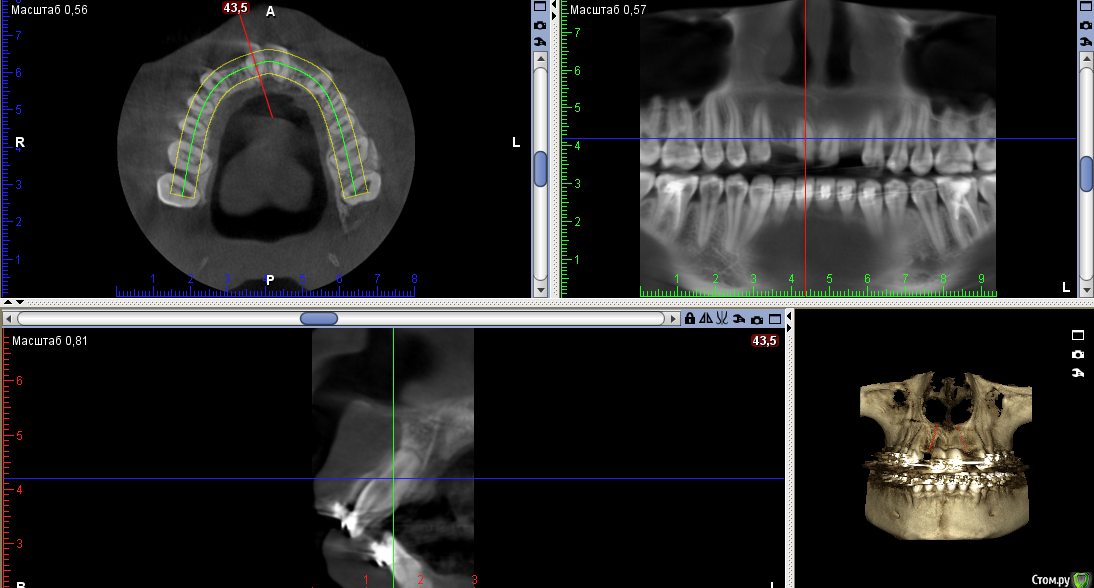

Тимур86 Опубликовано 22 сентября, 2016 Поделиться Опубликовано 22 сентября, 2016 Пациентка на ортодонтическом лечении.Нуждается в имплантации 12,22.В другой клинике предложили удалить 11 и 21 с костной пластикой,т.к. вестибулярно в области 11 отсутствует кость....Планируется установка Astra 3.0 в области 12 и 22 с использованием хирургического шабона,подсадкой СДТ и установкой ФДМ,через неделю временные коронки.Вопросы:1)зачем удалять 11 и 21? 2)нужна ли НКР? 3)можно ставить времяшки через неделю,учитывая подсадку СДТ? Ссылка на комментарий

колесников Опубликовано 22 сентября, 2016 Поделиться Опубликовано 22 сентября, 2016 Бред какой-то. Судя по снимку нет оснований ни для удаления,ни для нкр(с натяжкой 12),возможно визуально иначе. Поставил бы 3.5х9 ,сст и нагрузка. 2 Ссылка на комментарий